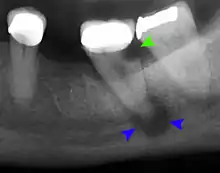

The periodontal ligament becomes inflamed and there may be pain when biting or tapping on the tooth. On an X-ray, bone resorption appears as a radiolucent area around the end of the root, although this does not manifest immediately.[10]: 228 Acute apical periodontitis is characterized by well-localized, spontaneous, persistent, moderate to severe pain.[6]: 125–135 The alveolar process may be tender to palpation over the roots. The tooth may be raised in the socket and feel more prominent than the adjacent teeth.[6]: 125–135

- Radiographs utilized to find dental caries and bone loss laterally or at the apex.

Decay (green) with apical abscess (blue)

Gutta-percha point indicating abscess origin